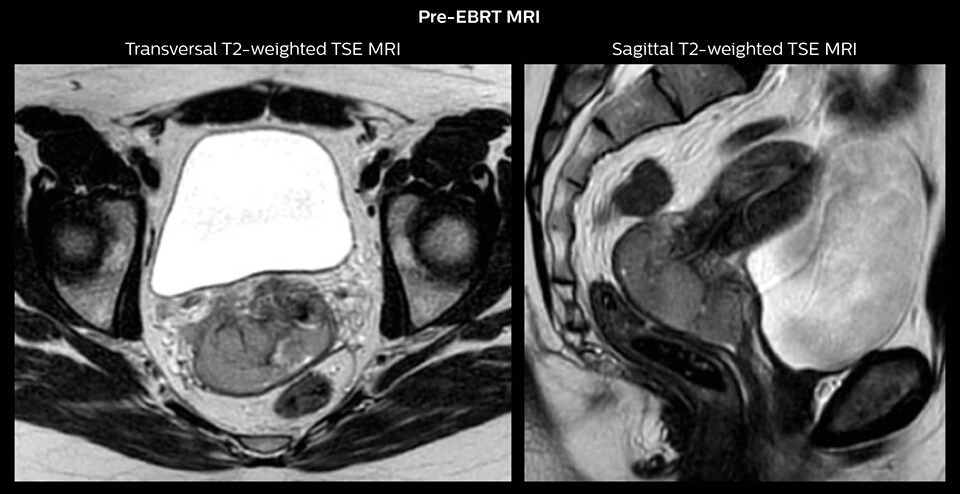

“In patients referred for cervical cancer treatment at our hospital, MRI has already been part of the diagnostic process. Before initiation of EBRT, PET-CT and MR treatment planning scans are acquired with the patient in treatment position on flat table top.

The images are fused and used for MRI-guided target definition of the primary tumor and for PET-guided definition of pathological lymph nodes.

Then we perform pre-brachytherapy MRI within one week before the first brachytherapy session. This MRI exam is done with a dummy applicator in place to establish the geometry we are going to see at brachytherapy. This MRI exam allows us to see how the tumor responded to EBRT and we also use it to decide which kind of applicator the patient needs. For instance, if we see a very advanced tumor with poor regression, we need a more advanced applicator which combines intracavitary and interstitial brachytherapy.”

Stage IIB cervix cancer patient with a primary tumor with width of 6.0 cm and proximal/distal infiltration of left/right parametria at diagnosis. The patient had one PET-positive external iliac lymph node.

The patient was treated with external beam radiotherapy (EBRT) and concomitant chemotherapy. EBRT was delivered as IMRT with daily IGRT and a total dose of 45 Gy in 25 fractions to the pelvis and 55/25 fractions to the PET-positive lymph node. There was good tumor response during therapy and towards the end of EBRT the primary tumor had regressed to 3.8 cm width and proximal parametrial infiltration.